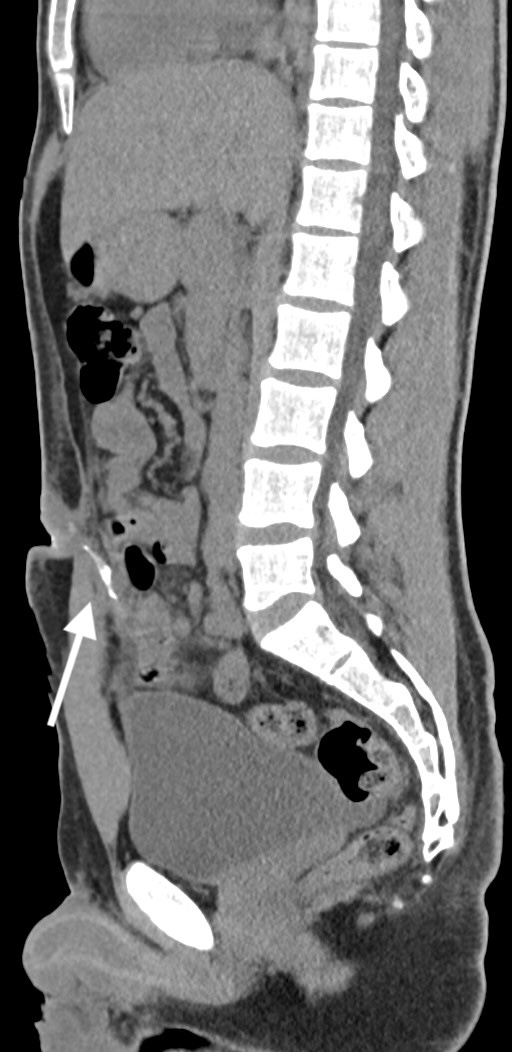

Three years after the appendectomy, the patient returned to the emergency department due to periumbilical pain and erythema that had persisted for three months. On further questioning the patient also reported intermittent diarrhea for one week, with no accompanying vomit or fever. During the physical examination, erythema and pain upon palpation of the umbilicus were observed. The blood tests showed no significant changes. Imaging with a CT scan and fistulogram through the umbilical granuloma allowed for the identification of a fistulous tract to a pericecal collection (figure 1-3). The patient was admitted and started on empiric antibiotic therapy with piperacillin and tazobactam.

Fig. 3: CT scan with fistulogram through the umbilical granuloma showing the fistulous tract to the cecum (white arrow) - sagital view.